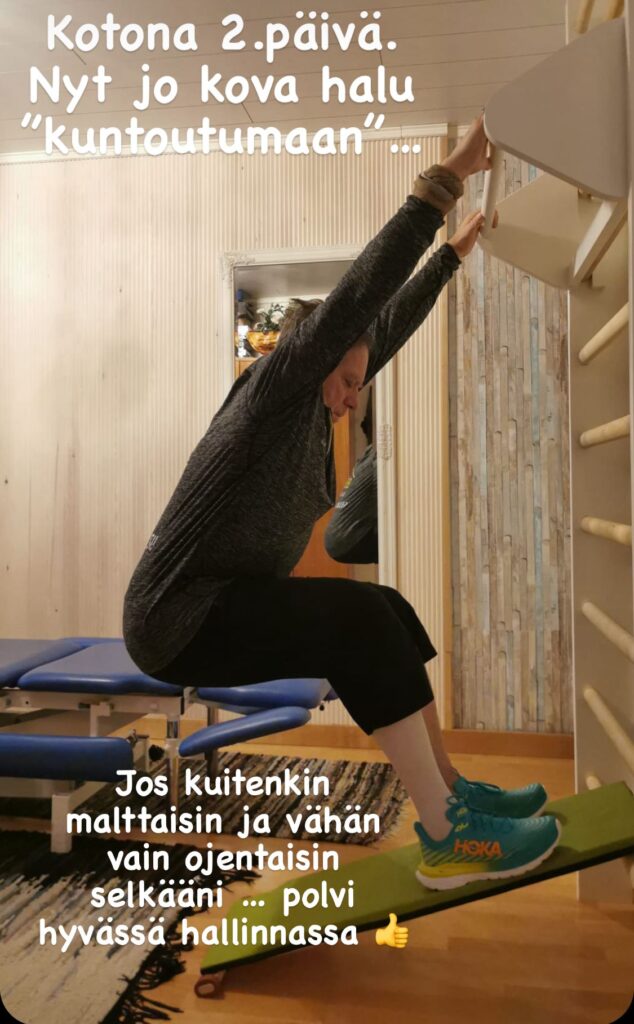

Aloitin hiljalleen polven kuntouttamisen. Merkiksi treenihetkestä puin päälleni treenivaatteet. Härkää oli otettava sarvista, vaikka tiesin, että ensimmäiset polven koukistukset olivat ne haastavimmat.

Onneksi olin jo vähän ennakoidusti asentanut kotiinkin Bodybow-puolapuut ja siirrettävän riipuntatangon. Harjoituksellisesti ne avasivat myös kaltaiselleni pitkän linjan fyssarille päivittäin uusia maailmoja.

Sijoittamalla astinlaudan alimmalle puolalle ja nostamalla kädet puolapuulle pystyin jatkamaan kävelytyyppistä liikettä kevennettynä. Välillä leikattu polvi toimi laudalla tukijalkana, välillä liikkeen suorittajana. Myös kevennetty kyykky pitäen käsillä puolapuista kiinni, tuntui venyttävän polven seutua. Vaikka polvessa oli ensi alkuun metallihakaset, kevennetyt liikkeet olivat hyvin tehtävissä puolapuun ja laudan ja jopa Bodybow-kaaren avulla. Kun hakaset oli sitten poistettu, liike helpottui entisestään ja pystyin ohjaamaan liikettä paremmin.

Luottamus polven tukeen parani selvästi näiden harjoitusten ansiosta. Katso video näistä liikkeistä.